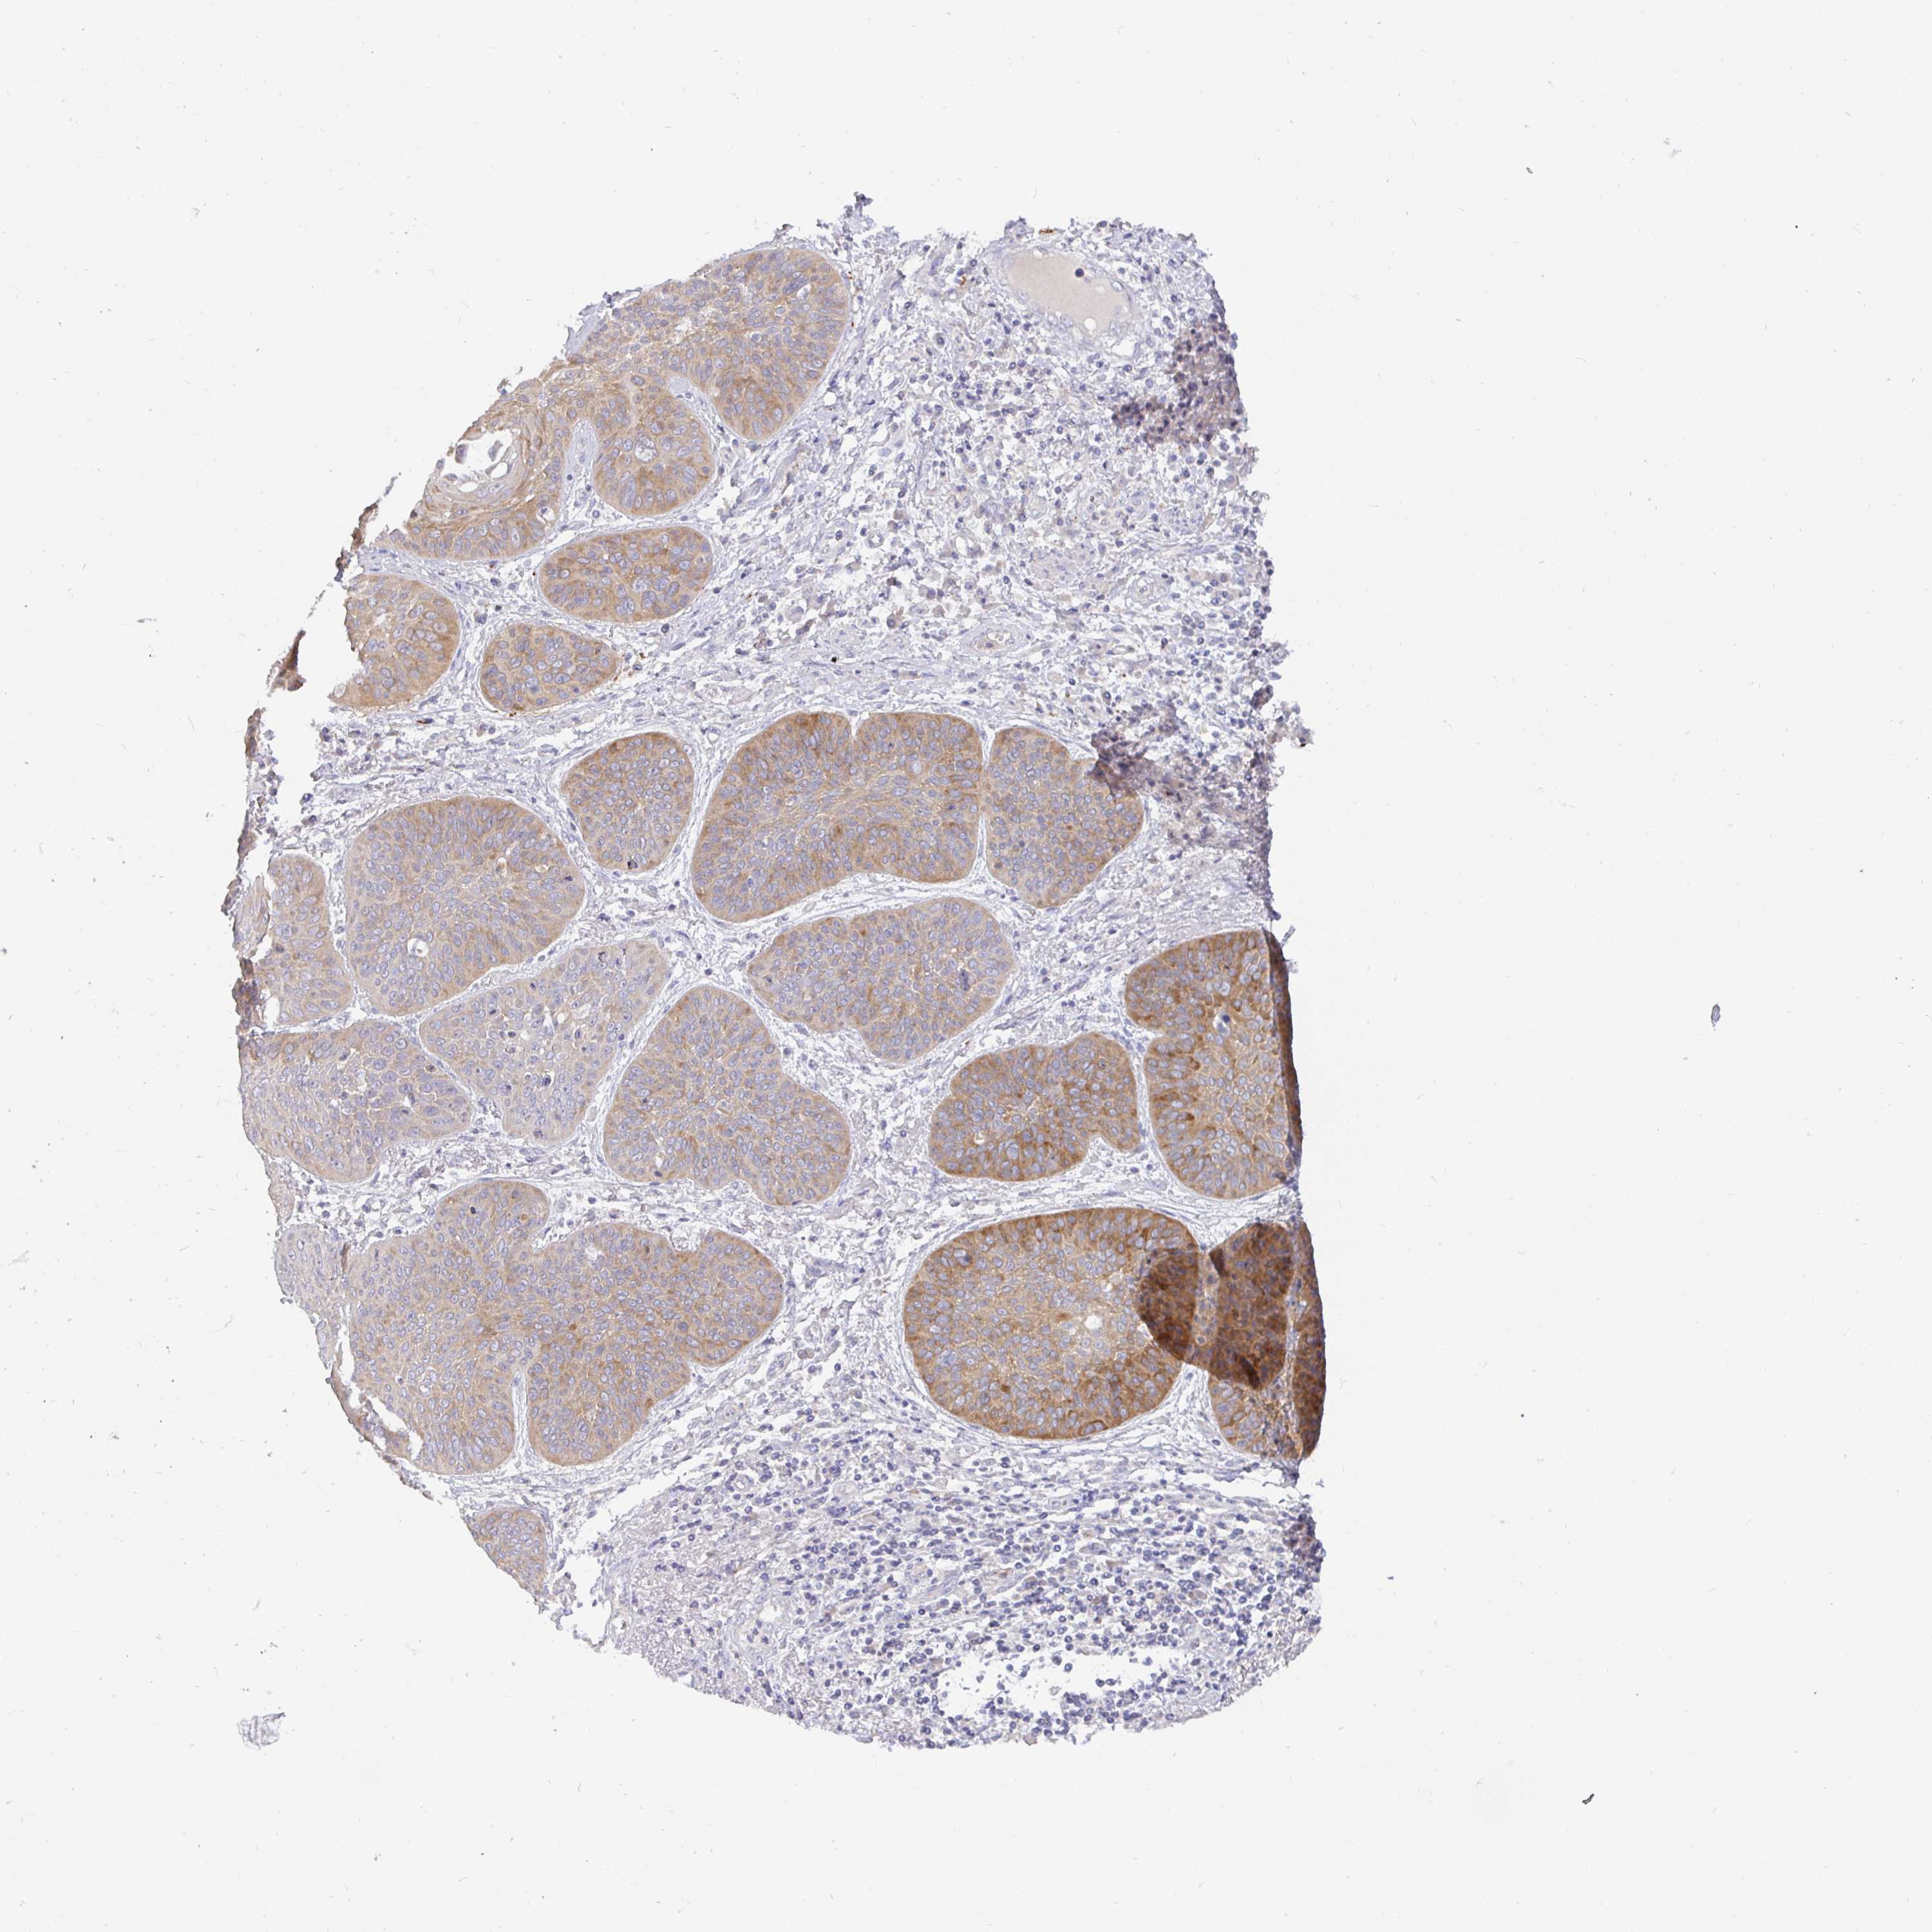

LUNG ADENOCARCINOMA (TCGA) - Interactive survival scatter ploti

The Survival Scatter plot shows the clinical status (i.e. dead or alive) for all individuals in the patient cohort, based on the same data that underlies the corresponding Kaplan-Meier plots. Patients that are alive at last time for follow-up are shown in blue and patients who have died during the study are shown in red.

The x-axis shows the expression levels (FPKM) of the investigated gene in the tumor tissue at the time of diagnosis. The y-axis shows the follow-up time after diagnosis (years). Both axes are complimented with kernel density curves demonstrating the data density over the axes. The top density plot shows the expression levels (FPKM) distribution among dead (red) and alive patients (blue). The right density plot shows the data density of the survived years of dead patients with high and low expression levels respectively, stratified using the cutoff indicated by the vertical dashed line through the Survival Scatter plot. This cutoff is automatically defined based on the FPKM cutoff that minimizes the p-score. The cutoff can be changed by dragging the vertical line or by entering a cutoff value in the square labeled "Current cut-off".

Under the Survival Scatter plot the p-score landscape (black curve; left axis) is shown together with dead median separation (red curve; right axis). Dead median separation is the difference in median mRNA expression between patients who have died with high and low expression, respectively. It is calculated as follows: median FPKM expression of dead patients with high expression - median FPKM expression of dead patients with low expression. This is intended to aid the user in visually exploring custom cutoffs and the associated p-scores and dead median separation.

Individual patient data is displayed and can be filtered by clicking on one or more of the category buttons on the top of the page. Categories describing expression level and patient information include: high, low, alive, dead, female, male and tumor stages. The scale of the x-axis can be toggled between linear and log-scale by clicking on the "x log" button. Mouse-over function shows TCGA ID, patient information and mRNA expression (FPKM) for each patient.

& Survival analysisi

Kaplan-Meier plots summarize results from analysis of correlation between mRNA expression level and patient survival. Patients were divided based on level of expression into one of the two groups "low" (under cut off) or "high" (over cut off). X-axis shows time for survival (years) and y-axis shows the probability of survival, where 1.0 corresponds to 100 percent.

KIF21A is not prognostic in Lung Adenocarcinoma (TCGA)

Best expression cut offi

Based on the FPKM value of each gene, patients were classified into two groups and association between prognosis (survival) and gene expression (FPKM) was examined. The best expression cut-off refers the FPKM value that yields maximal difference with regard to survival between the two groups at the lowest log-rank P-value. Best expression cut-off was selected based on survival analysis .

When clicking on this number, the vertical dashed line indicating cut-off, the interactive survival plot, and the Kaplan-Meier curve will be adjusted to show results based on the best expression cut-off.

: 5.73

P scorei

Log-rank P value for Kaplan-Meier plot showing results from analysis of correlation between mRNA expression level and patient survival.

N/A

TCGA RNA samplesi

RNA-seq data is reported as average FPKM (number Fragments Per Kilobase of exon per Million reads), generated by the The Cancer Genome Atlas (TCGA) .

Normal distribution across the dataset is visualized with box plots, shown as median and 25th and 75th percentiles. Points are displayed as outliers if they are above or below 1.5 times the interquartile range. FPKM values of the individual samples are presented next to the box plot.

Average pTPM 10.9

Number of samples 497